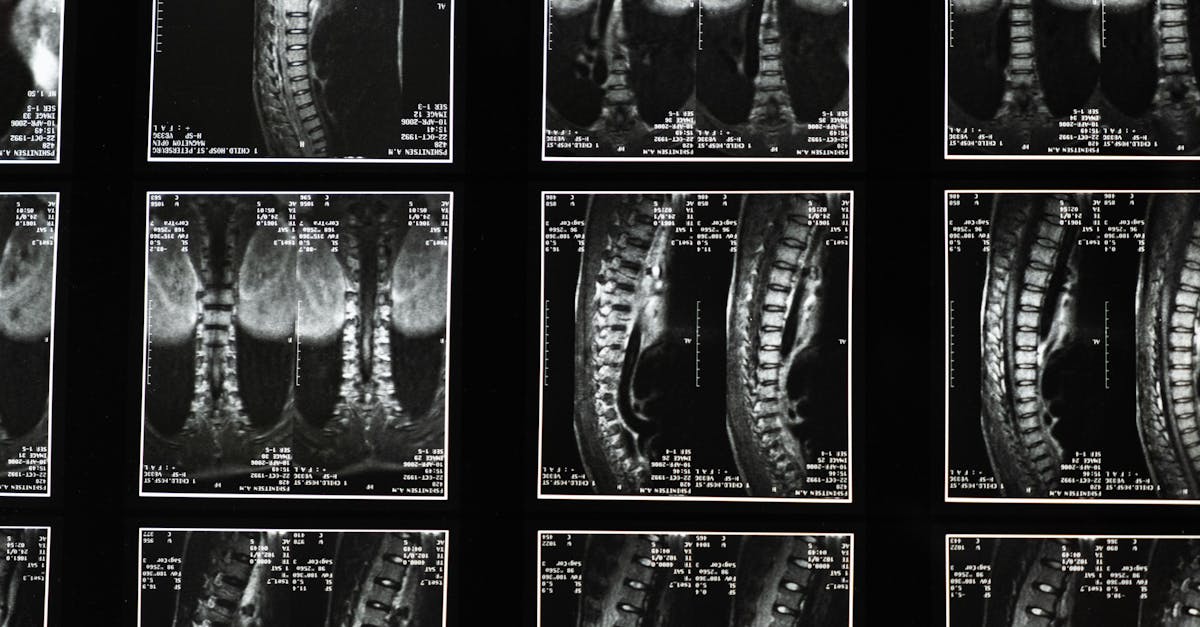

La décompression neurovertébrale utilise un appareil spécialisé pour étirer la colonne vertébrale. Ce procédé crée un espace entre les vertèbres. En diminuant la pression sur les nerfs et les disques, cette méthode améliore la circulation sanguine et favorise le bon fonctionnement des tissus. Cela permet de traiter efficacement les douleurs chroniques et d’aider à la réhabilitation.

Un des objectifs principaux après une chirurgie est généralement de retrouver une mobilité adéquate. Grâce à la décompression neurovertébrale, les patients bénéficient d’une augmentation de leur amplitude de mouvement. En créant un espace entre les vertèbres, cette méthode réduit les contraintes exercées sur la colonne vertébrale et favorise un rétablissement plus rapide. Cela permet aux patients de reprendre progressivement leurs activités normales sans douleurs entravantes.

En plus de soulager la douleur et d’améliorer la mobilité, la décompression neurovertébrale favorise une meilleure circulation sanguine. En réduisant l’inflammation et en augmentant l’apport sanguin vers les tissus affectés, cette méthode stimule la guérison et accélère le processus de réhabilitation. Cela est particulièrement bénéfique pour les patients ayant subi des interventions sur la colonne vertébrale, où les tissus environnants nécessitent un soin attentif.